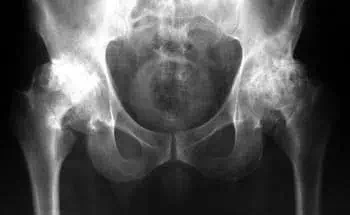

Acum 2 ani, m-am confruntat pentru prima dată cu dureri ușoare în genunchi și șold. Durerea nu a fost puternică, nu i-am acordat prea multă atenție... După cum s-a dovedit, bolile articulare sunt foarte grave și trebuie tratate imediat, nu amânate cum făceam eu! Într-o zi foarte obișnuită, am simțit o durere nu foarte puternică, dar ascuțită în genunchi, iar articulația șoldului a început să doară serios, am crezut că nu este nimic strașnic, va dispărea ca de obicei. Am cumpărat medicamente și am început să le aplic. Am îndurat timp de aproximativ 1 săptămână, starea mea a început să se înrăutățească brusc, durerea a devenit insuportabilă, durerea acută a început în articulația șoldului, am decis să merg la medic pentru prima dată. Mi-au făcut un diagnostic ieftin, iar medicul meu s-a uitat la rezultatele examinării și a spus:

"De ce mai înainte ați ignorat simptomele? Aveți artroză! Artroza, dacă doriți să nu deveniți invalid, trebuie îndăpărtată cu o intervenție chirurgicală pe șold și genunchi!”

img img